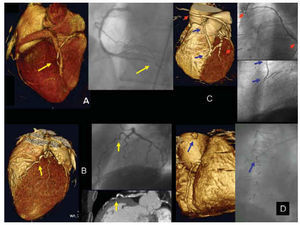

Por último, en los injertos coronarios con escaso número de segmentos analizados (9 segmentos valorables por coronariografía, al igual que también 9 segmentos por TCDM), la sensibilidad y especificidad fueron ambas del 100% (fig. 2 A-D).

Fig. 2. Lesiones arteriales coronarias visualizadas por tomografía computarizada con detectores múltiples (TCDM) y coronariografía invasiva. A: lesión estenótica significativa en el tercio distal de la arteria descendente posterior (flecha amarilla); aun siendo un vaso de mediano tamaño, la lesión se detecta correctamente por TCDM en la reconstrucción 3D «renderizada» (izqda.), que se corresponde con la coronariografía invasiva (dcha.). B: lesión no significativa en el segmento proximal, tortuoso de la arteria descendente anterior (flecha amarilla); en la izquierda, TCDM con reconstrucción 3D «renderizada» en la que se visualiza la localización exacta de la lesión con una excelente correspondencia en la coronariografía invasiva (dcha. sup.). La TCDM añade información, no siempre evidente en la angiografía invasiva, del contenido cálcico de la arteria en esta localización (dcha. inf.). C: injertos coronarios permeables con su correspondencia en la coronariografía invasiva; injerto de arteria mamaria interna a arteria descendente anterior (flechas azules) e injerto aortocoronario de vena safena interna a arteria obtusa marginal de circunfleja (flechas rojas). D: injerto aortocoronario de vena safena interna a arteria obtusa marginal de circunfleja, ocluido en su origen. En la imagen 3D «renderizada» de TCDM (izquierda) puede apreciarse la presencia de un muñón en la pared de la aorta ascendente (flecha azul) correspondiente a la oclusión del injerto, que no deja progresar el contraste.

Nuestra experiencia parece indicar que la TCDM tiene un papel destacado en el estudio de los injertos coronarios, ya sea porque éstos son vasos de mayor calibre o de menor movimiento en el ciclo cardíaco, y la buena calidad de las imágenes obtenidas21 (fig. 2 C y D) hace que el poder diagnóstico de la técnica sea en estos casos elevado, tanto en nuestro estudio, sobre un escaso número de injertos, como en otros22. Su carácter no invasivo y la posibilidad de realizar estudios de seguimiento confiere un valor añadido a la técnica. Debe mencionarse, no obstante, una potencial limitación en el estudio de los injertos coronarios, como es la valoración de la porción proximal de los injertos de arteria mamaria interna, ya que ésta no se halla incluida en el volumen obtenido con el protocolo utilizado en este estudio por razones de duración de la apnea requerida. No obstante, como se ha demostrado23, la proporción de lesiones obstructivas desarrolladas en los segmentos proximales de la arteria mamaria interna es escasa en la práctica clínica.